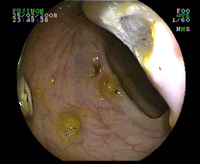

Diverticule du colon